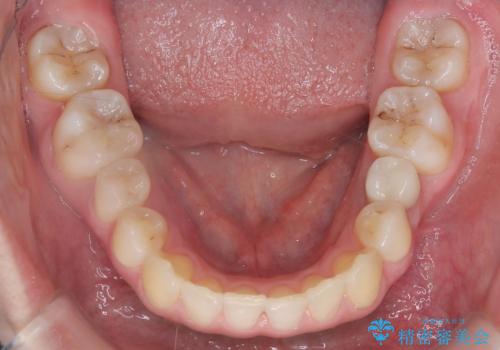

- 患者様は、前歯のガタガタ(叢生)と左下5番の欠損部が気になるとのことで来院されました。診断の結果、インビザラインを用いて前歯の叢生を整えながら、左下5番の欠損部にはインプラント治療を計画しました。矯正治療により、歯並びを改善すると同時に、噛み合わせのバランスも向上させることを目標としました。矯正期間とインプラントの治療計画を並行して進めることで、患者様のご希望に応えるプランを立てました。

前歯の叢生改善のため、インビザラインによる透明で目立たない矯正装置を使用しました。治療中は、歯の移動による負担を最小限に抑えつつ、歯列全体のバランスを考慮して進めました。左下5番の欠損部には、矯正終了後にインプラントを埋入し、自然で機能的な咬合を回復しました。治療期間中、患者様には装置の正しい装着と日々の清掃を徹底していただき、歯肉やインプラント周囲の健康を保つようサポートしました。結果として、美しい歯並びと快適な噛み合わせを両立させることができました。